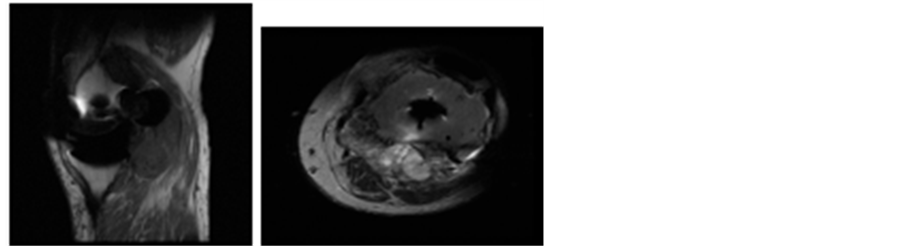

Liposarcoma is the second most common soft tissue sarcoma in adults, presenting typically between the age of 40 and 60, and commonly arising in deep muscle masses. Around 40% of these tumours occur in the lower extremity [15] . Morphologically liposarcomas can be classified as well differentiated, myxoid/round, and pleomorphic. Myxoid tumours comprise 50% of liposarcomas and have intermediate malignant potential and local recurrence is common without full excision. The most common presentation is a painless enlarging mass. On MR imaging, Figure 7, they typically have an inhomogeneous appearance, may appear cystic, and they typically have a fat content of less than 25%, making them potentially difficult to distinguish from popliteal cysts.

Figure 7. Myxoid Liposaroma. (a) T1 sagittal; (b) T2 sagittal; (c) T2 axial sequences. A pseudoneck is seen at its anteromedial aspect mimicking a popliteal cyst.